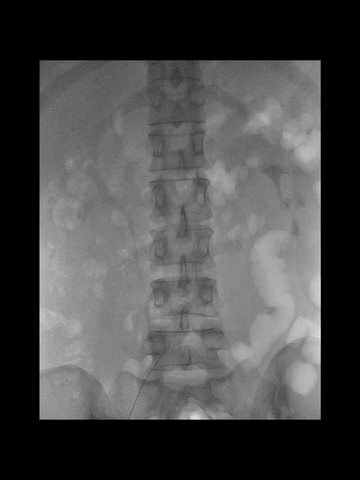

右股动脉穿刺置入8F短鞘,125cm长度5F多功能管塑成西蒙管头端形状,与6F长鞘(Cook,90cm)组成同轴,导丝导引下,5F管进入左锁骨下动脉,而后成其头端成西蒙管形,进入弓内。

耐心冒烟下,调整导管头在无名动脉内指向左侧,同时回拉导管,进入右CCA,后上高导丝,长鞘沿5F管顺利进入右CCA,后在导管导丝导引下,长鞘头端上高到右C1远端,建立可靠的治疗通路。